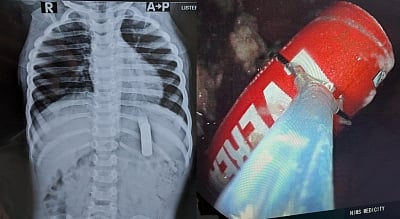

அங்கு நடந்தவற்றை மருத்துவர்களிடம் கூறியுள்ளனர். உடனே மருத்துவர் குழு சிறுவனுக்கு அறுவை சிகிச்சை செய்ய அனைத்து நடவடிக்கைகளையும் மேற்கொண்டது. பிறகு 20 நிமிடத்திலேயே எண்டோஸ்கோபி சிகிச்சை மூலம் சிறுவன் வயிற்றிலிருந்து பேட்டரியை மருத்துவர்கள் வெளியே எடுத்தனர்.

தற்போது சிறுவன் நலமுடன் இருப்பதாகவும், பேட்டரி வயிற்றுப் பகுதியைத் தவிற வேறு இடத்தில் சிக்கி இருந்தால் சிறுவன் உயிருக்கே ஆபத்தாக இருந்திருக்கும் என மருத்துவர்கள் தெரிவித்துள்ளனர். சிறுவன் விழுங்கிய பேட்டரியின் அளவு 5 செ.மீ நீளமும்,1.5 செ.மீ அகலமும் கொண்டது என்பது குறிப்பிடத்தக்கது.